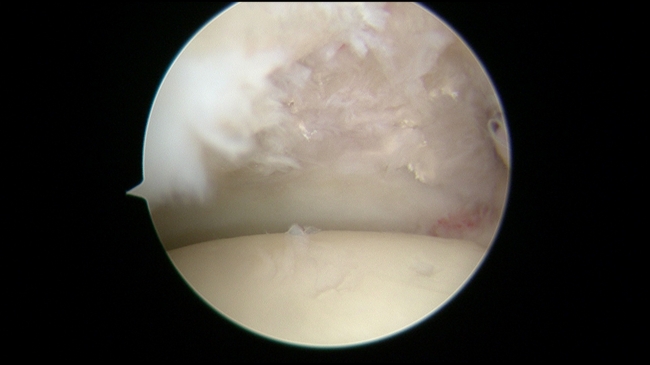

“当时李先生的疼痛已经非常剧烈,注射曲马多都无法缓解,我们检查发现,他踝关节软骨剥脱严重,同时还合并有痛风症状,尿酸也比较高。” 骨二科主任李杨介绍,“针对李先生这种慢性踝关节损伤的情况,采用踝关节镜技术进行微创治疗,是目前最合适的治疗方案。”

踝关节镜是近年来兴起的一种踝关节疾病的微创治疗方法,通过2个不到1cm的小切口,将关节镜伸到踝关节内处理踝关节疾病,可实现直视下观察踝关节内部结构的变化,并做出较以往切开手术更准确的判断,针对病因进行积极处理。同时还具有创口小而美观,术后关节囊和韧带的粘连较小,手术部位疼痛少,住院时间缩短,关节功能恢复快等优势。随着器械的发展和人们对疾病的深入认识,骨关节镜的适应症越来越广泛,但相比膝关节镜而言,踝关节的关节间隙更为狭窄,踝关节镜的操作空间也更为有限,所以需要具有丰富经验的医生才能操作。

湘南学院附属医院运动骨科学团队,紧跟医学发展前沿,掌握先进医学技术,对于膝关节、肩关节、踝关节等相关疾病的关节镜微创治疗具有丰富经验。经过前期周密安排,李杨主任医师和彭启华主治医师联手在 3月18日顺利为李先生实施了右踝关节镜下探查+滑膜切除术+软骨修复术。手术开展得十分成功,术后患者的踝关节疼痛症状随即减轻,术后第二天即可下地活动。被踝关节剧痛困扰了一年多的李先生,终于露出了久违的笑容。